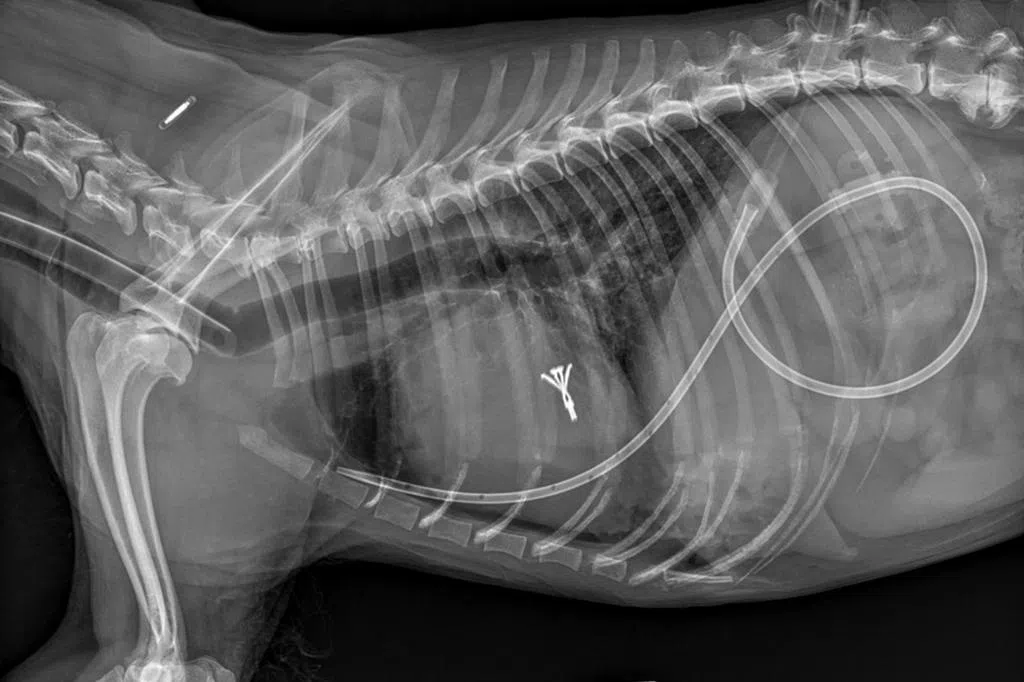

Atlas兽医诊所的周浩廷医生,是医疗指导原则工作小组的其中一名负责人。他受访时说,过去非常规疗法多靠家人朋友之间口耳相传,但随着社交媒体越来越普及,这类信息传播更快更广。尤其是一些声称靠自然疗法治愈疾病的“成功案例”,更容易引发“病毒式”传播,影响广泛。

新指导原则出台后,就能为兽医和宠物主人提供一个科学且规范的依据,来评估和选择适合的治疗方案,避免盲目相信未经验证的信息或受误导。